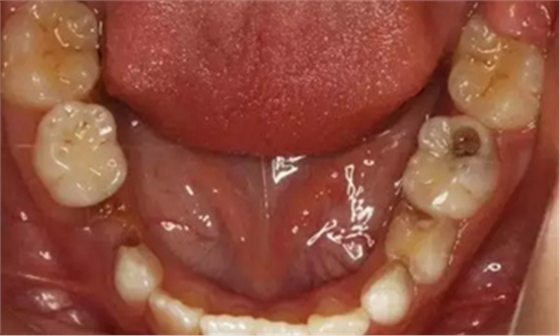

1、 患者 男 7歲 右下乳IV因齲早失

3、曲面斷層片 示恒牙萌出間隙不足